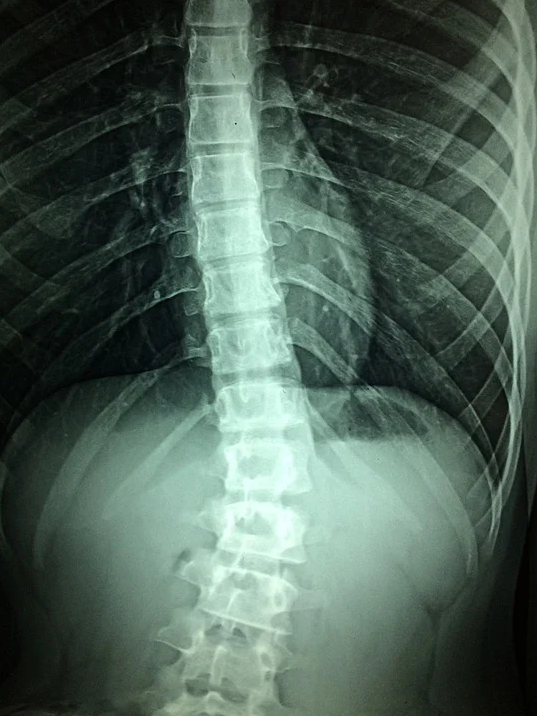

근골격계 관련 검사

경추/ 요추/ 척추 관련 MRI & X 레이

근골격계 질환의 경우 보통 환자가 인지하는 경우가 많고, 꼭 검강검진이 아니더라도 생활하면서 이상징후를 발견할 수도 있고, 상시 진단 및 관련 치료가 가능하기 때문에 꼭 검진 항목으로 진행해야 하는 것은 아닙니다.

추천하지 않습니다.